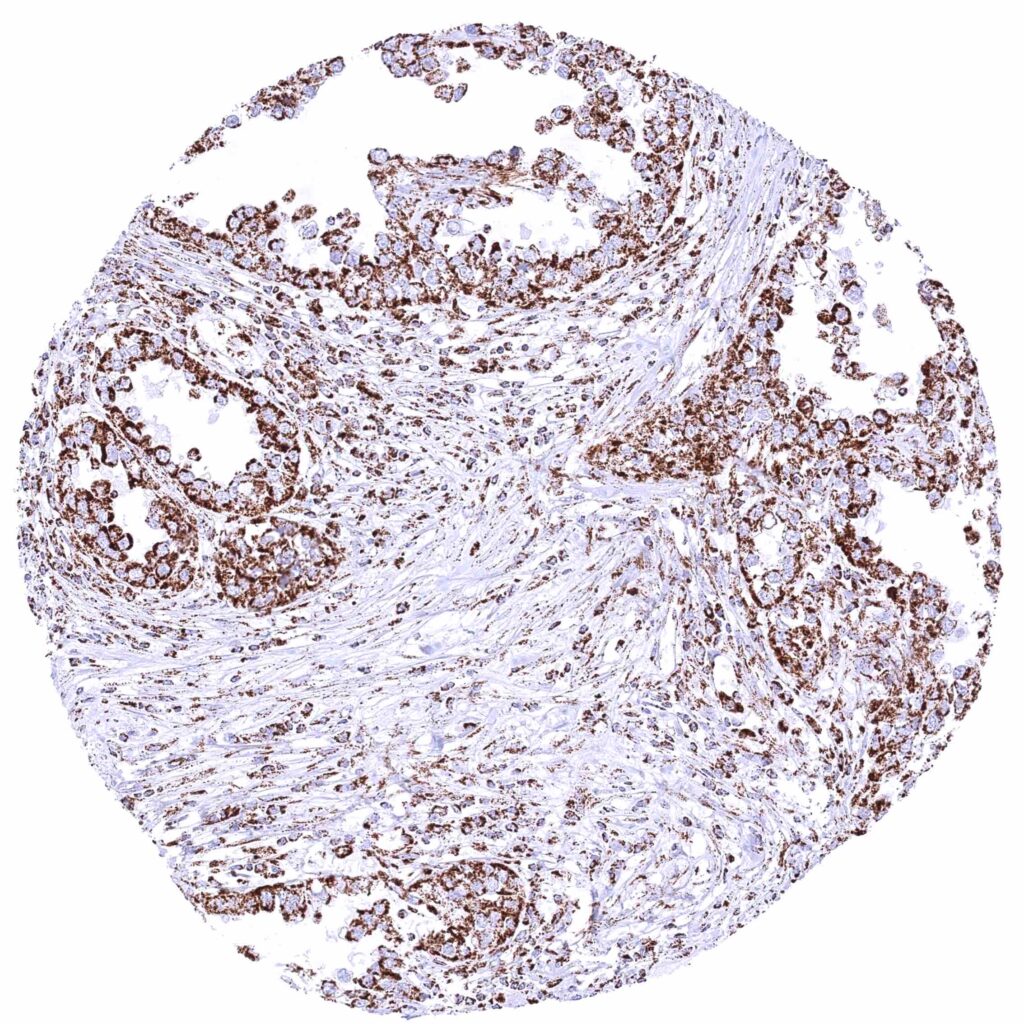

Urinary bladder – Muscle-invasive urothelial carcinoma with moderate cytoplasmic ATP5J staining of all tumor cells.